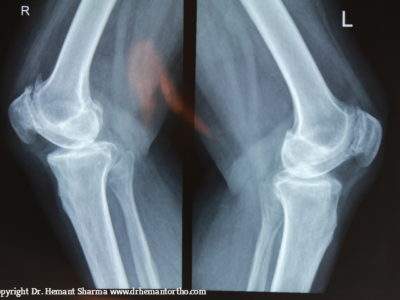

The diagnosis process will also include several imaging tests like ultrasound, MRI, CT Scan, and X-ray of the adjacent areas.

         Severe Damage: The doctor recommends knee replacement surgery if an x-ray report suggests severe knee damage. The severe damage cannot be cured through medication. Therefore, knee replacement surgery is the best solution.

PRE-OPERATIVE